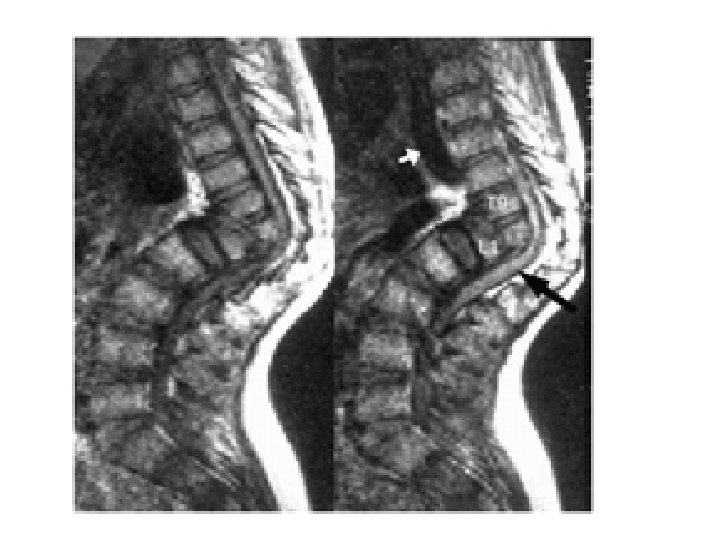

Tuberculosis of the Spine- Pott’s Disease • As a form of extrapulmonary tuberculosis that impacts the spine, Pott’s disease has an effect that is sometimes described as being a sort of arthritis for the vertebrae that make up the spinal column. • More properly known as tuberculosis spondylitis, Pott’s disease is named after Dr. Percivall Pott, an eighteenth century surgeon who was considered an authority in issues related to the back and spine • . Pott's disease is often experienced as a local phenomenon that begins in the thoracic section of the spinal column. Early signs of the presence of Pott’s disease generally begin with back